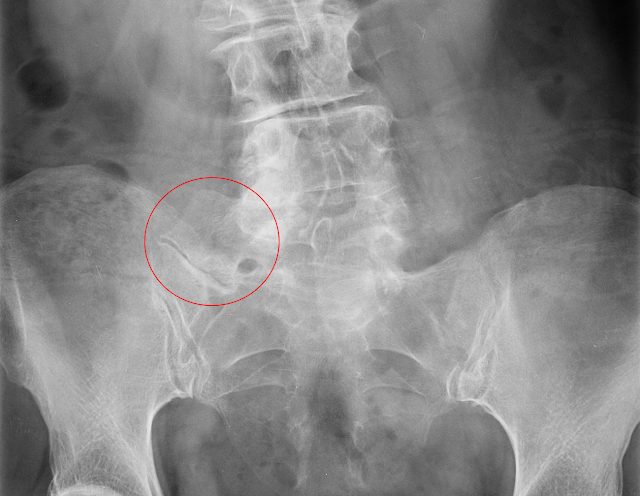

- X光片:能夠清楚顯示第五腰椎與骶骨或髂骨之間的骨性融合情況,這是 Bertolotti Syndrome 的關鍵診斷依據,另外側面 X 光片顯示 LSTV 的典型外觀,過渡椎體呈現方形及過渡椎間盤高度減少